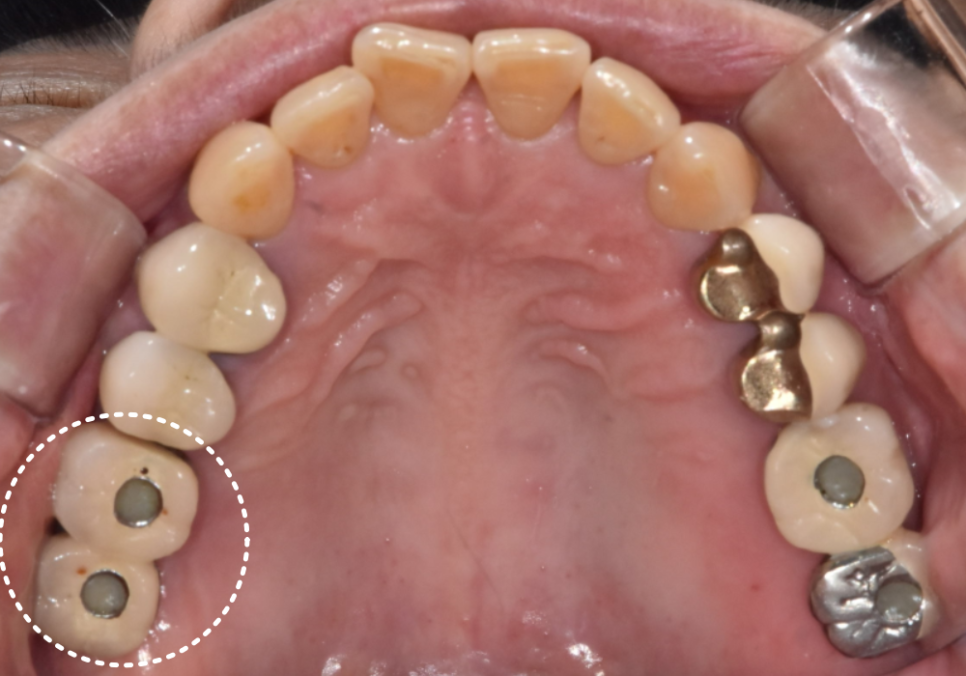

얼마 전 왼쪽 아래 임플란트 끝부분이 깨져서

내원하신 환자분이 계셨어요.

깨진 것도 문제였지만,

예전에 비해 음식물도 너무 잘 끼고

불쾌한 냄새가 나는 것 같다고 말씀해주셨는데요~

입안을 자세히 살펴보니,

보철물이 많이 닳아 낮아지면서

임플란트 나사 구멍이 드러나 있었고,